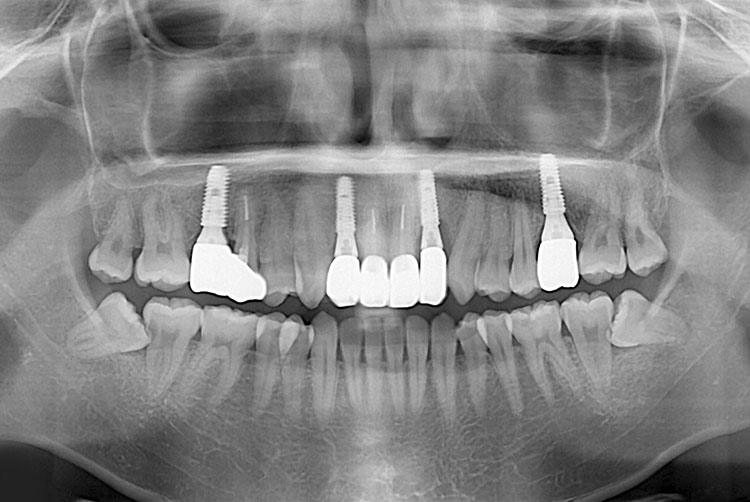

[임플란트] 임플란트

치료후 : 2018-04-13

세종치과는 많은 환자와 다양한 케이스를 바탕으로 항상 편안한 임플란트 수술을 제공하고자 노력하고,

오래동안 튼튼히 쓸 수 있는 임플란트 수술을 가장 큰 목표로 삼고 있습니다.